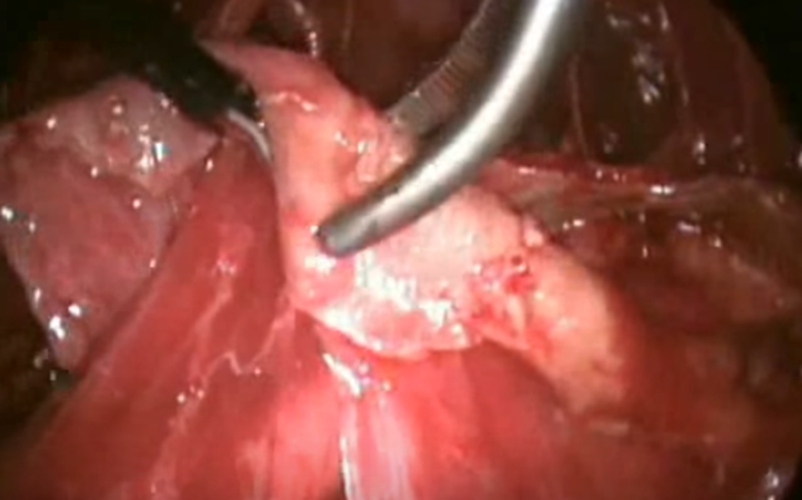

結核性胸膜炎胸腔鏡

結核性胸膜炎胸腔鏡的